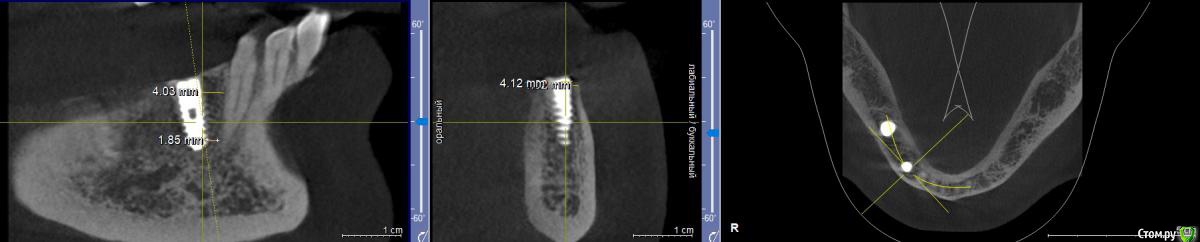

zumanok Опубликовано 11 декабря, 2019 Поделиться Опубликовано 11 декабря, 2019 Здравствуйте доктора, установлен имплант 5 недель назад. 4.2 на 11.5 Область 3.4. сделать проверочное КТ не было возможности. На новом снимке обнаружилось что увел имплантат щечнее чем планировал и стенка меньше 1мм (на фото самая тонкая стенка). Так же отмечено что имплант несного фонит.Как вы посоветуете? 1.Убрать и переставить сразу немного медиальнее(но слабо себе представляю) или Переставить через 2 месяца. 2. Оставить так. Благодарю за советы Ссылка на комментарий

diesel87 Опубликовано 11 декабря, 2019 Поделиться Опубликовано 11 декабря, 2019 Отчасти согласен с коллегами, но все таки не могу верно оценить заглубление и близость к 33 по этим двум срезам, может у вас есть снимок рг прицельный или ортов? Ссылка на комментарий

zumanok Опубликовано 11 декабря, 2019 Автор Поделиться Опубликовано 11 декабря, 2019 (изменено) Отчасти согласен с коллегами, но все таки не могу верно оценить заглубление и близость к 33 по этим двум срезам, может у вас есть снимок рг прицельный или ортов?На сообщение выше. Планируется мост 4.4-4.6. В области 4.6 имплант устраивает. Изменено 11 декабря, 2019 пользователем zumanok Ссылка на комментарий

diesel87 Опубликовано 11 декабря, 2019 Поделиться Опубликовано 11 декабря, 2019 Сейчас понимаю что подвинуть медиально не получится, только угол поменять немного, т.к. корень соседа мешает.При этом не смогу сразу зафиксировать. Для позиции премоляра расстояние до клыка очень большое, нужно переставить имплант с медиальным наклоном по оси клыка и заглубить еще, возможно стоит взять имплант длинной 10 мм, не вижу точного расстояния до ментального. Ссылка на комментарий

zumanok Опубликовано 11 декабря, 2019 Автор Поделиться Опубликовано 11 декабря, 2019 Для позиции премоляра расстояние до клыка очень большое, нужно переставить имплант с медиальным наклоном по оси клыка и заглубить еще, возможно стоит взять имплант длинной 10 мм, не вижу точного расстояния до ментального.Ментальное отверстие дистальнее мм на 5. А почему покороче? стоит 11.5 Ссылка на комментарий

diesel87 Опубликовано 11 декабря, 2019 Поделиться Опубликовано 11 декабря, 2019 Ментальное отверстие дистальнее мм на 5. А почему покороче? стоит 11.5По этому срезу я вижу что канал как бы заканчивается на 5 мм дистальнее, но это не значит что он не идет дальше медиальнее. Почему короче, потому что нужно заглубить чуть имплант и примерно на те 1,5-2 мм на которые вы возьмете короче имплант, тем. самым точно не попадете в канал (если он проходит близко ниже). А вообще длиннее 10 мм при отсроченной имплантации я не ставлю. Ссылка на комментарий